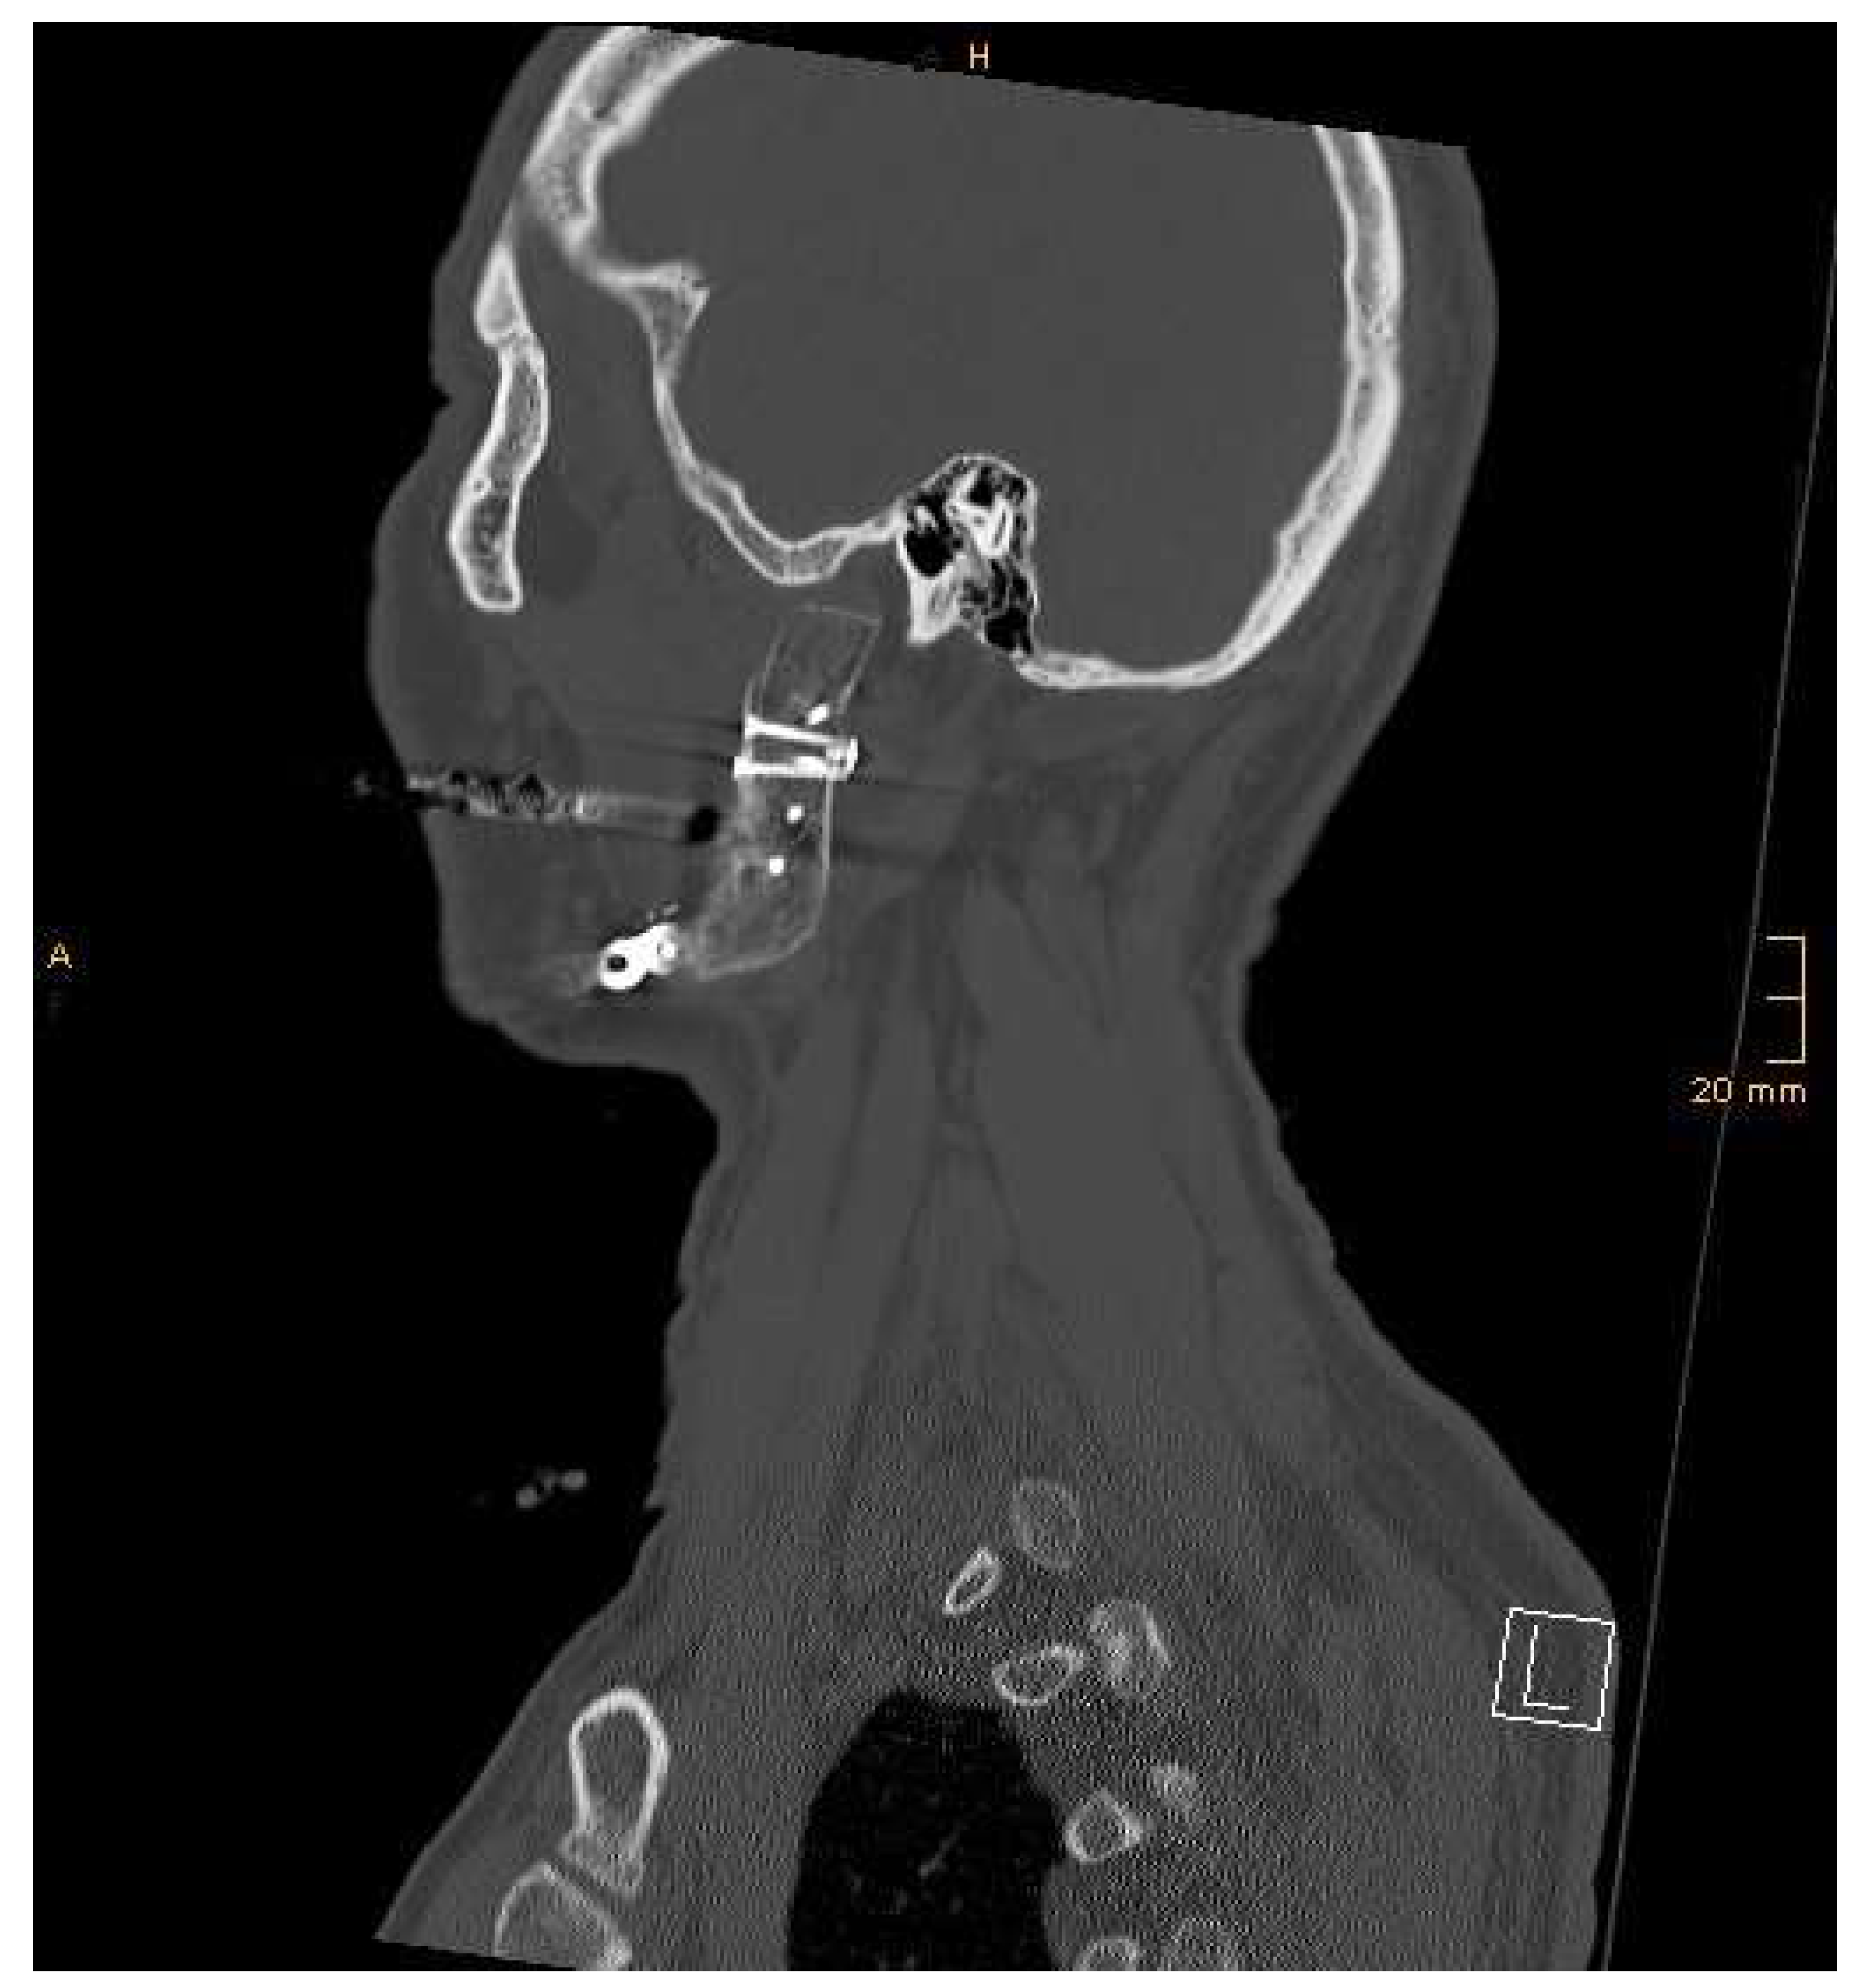

2.2. Surgical Procedure

3. Results

| Patient 1 | 59 | f | Therapy-refractory osteomyelitis | 80 | No | 9 | (Hypo)pigmentation 3, relief 4, all others 0 | Nearly no complaint | 5 mm | 40 mm | 52 | No |

| Patient 2 | 63 | m | Extended recurrent odontogenic keratozyst | 80 | No | 10 | Pliability 1, all others 0 | No complaint | 40 mm | 40 mm | 50 | No |

| Patient 3 | 17 | f | Goldenhar syndrome | 80 | Rarely light pain | Cannot be assessed | Not applicable due to skin transfer | Cannot be assessed | 20 mm | 35 mm | 70 | Yes |

| Patient 4 | 51 | m | Adenocarcinoma of the parotid gland | 80 | Joint noise, no pain | 8 | Not applicable due to skin transfer | Nearly no complaint | 40 mm | 35 mm | 24 | Yes |